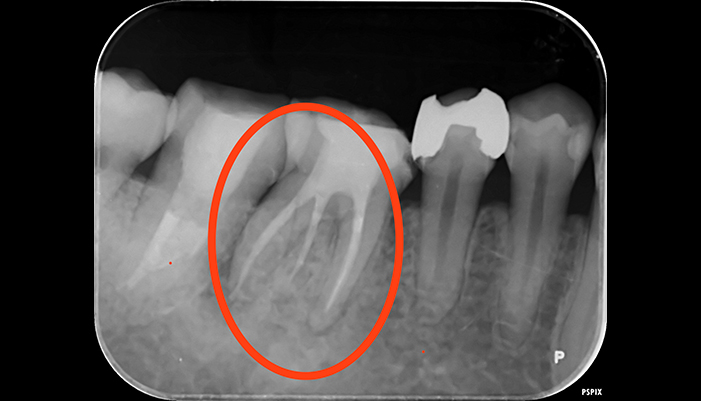

治療前

治療後

| 主訴 | 虫歯がある。根の管が細すぎて見当たらない。 |

|---|---|

| 治療期間 | 1回 |

| 費用 | 再根管治療132,000円(税込)+ ファイバーコア44,000円(税込)= 176,000円(税込) |

| 治療内容 |

ラバーダムを用いて無菌的な環境下で根管治療を行いました。 マイクロスコープ下で虫歯を完全に取り切り、根の管の細さが0.06mm程度になっていたため慎重にNiTiファイルを用いて根管形成を行い、 薬液や超音波器具による洗浄、体に馴染みの良い材質による充填、被せ物を支え、再感染しないように土台を立てました。 |